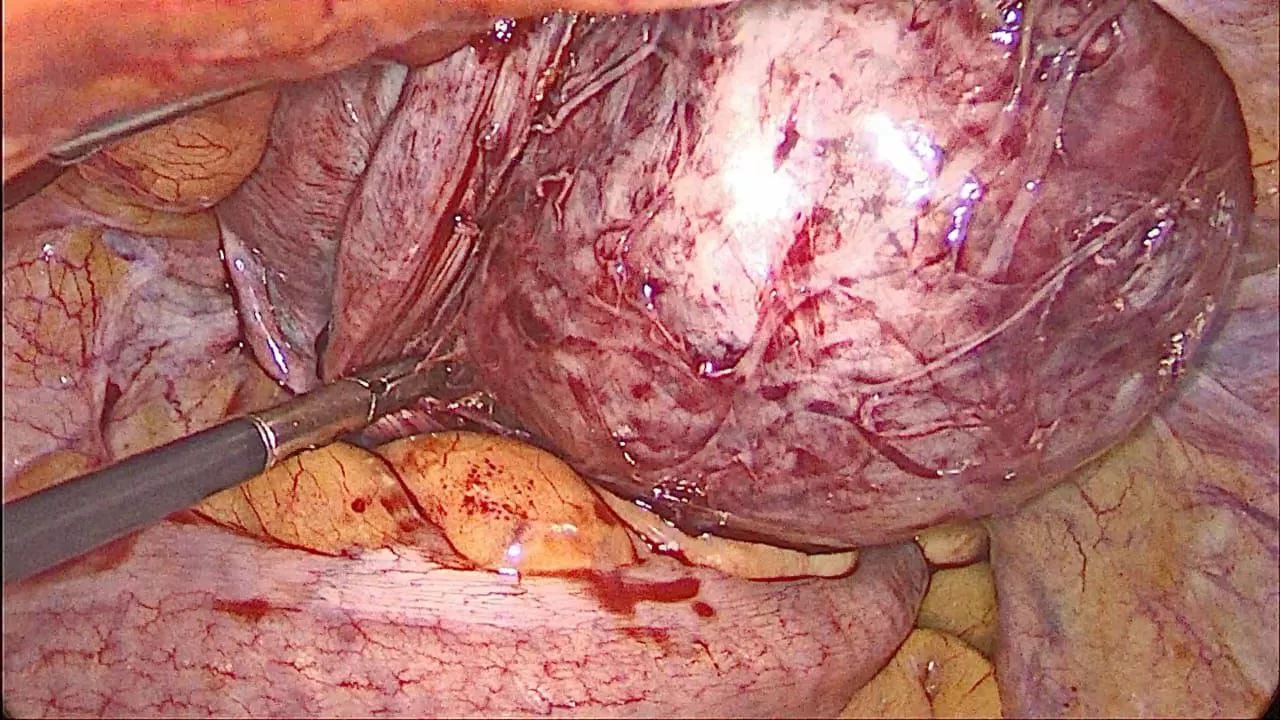

- The posterior wall fibroid was identified and vasopressin was infiltrated to reduce intraoperative bleeding.

- A serosal incision was made, and the fibroid was enucleated using sharp and blunt dissection assisted by Ligasure.

- The uterine incision was sutured in layers to restore anatomical integrity.